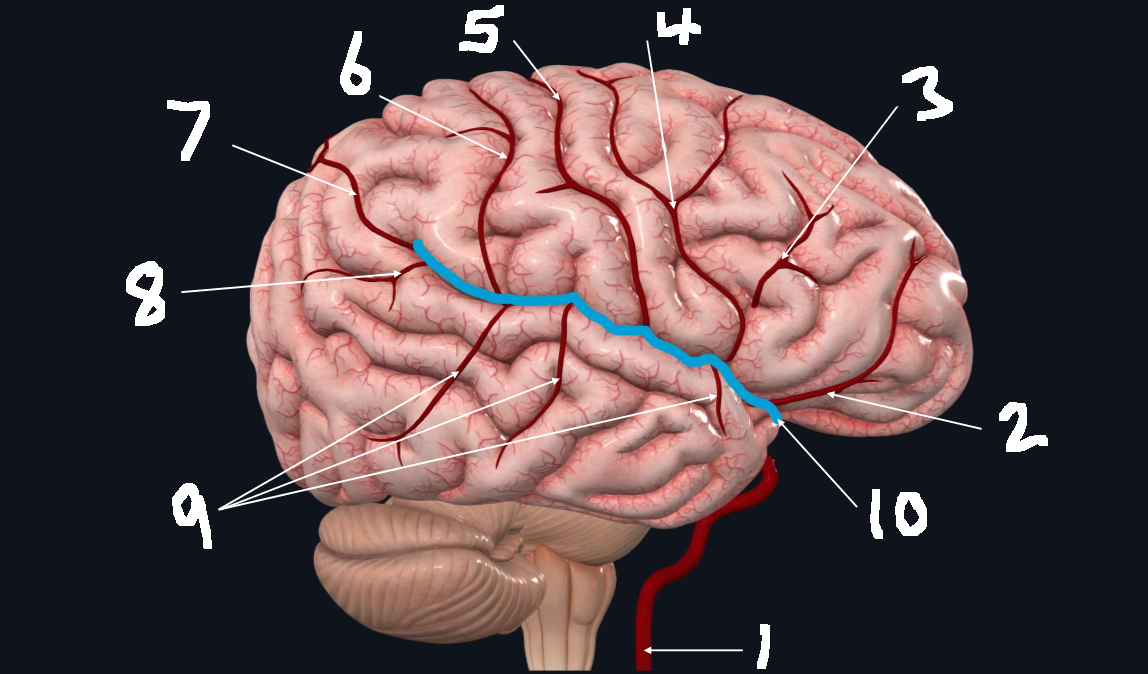

What is 1?

internal carotid artery

What is 2?

orbitofrontal artery

What is 3?

prefrontal artery

What is 4?

precentral artery

What is 5?

central artery

What is 6?

postcentral artery

What is 7?

posterior parietal artery

What is 8?

angular artery

What is 9?

temporal arteries (anterior, middle, posterior)

What is 10?

lateral cerebral fissure